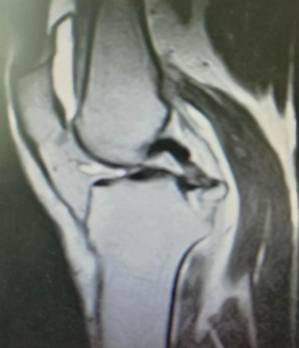

关节专科现有主任医师4名,副主任医师1名,主治医师1名,硕士4名。在股骨头坏死、髋臼发育不良、髋关节骨性关节炎、股骨髋臼撞击综合症、膝关节骨性关节炎、类风湿性关节炎、强直性脊柱炎合并髋关节强直、股骨颈骨折、膝关节运动损伤、肩关节运动损伤、足踝损伤和畸形等骨关节疾病的中西医结合治疗方面独具特色。

手术技术上与国内领先医院接轨,并不断创新。系统开展膝关节骨性关节炎的阶梯治疗方案,早期采用中医中药、理疗、肌力训练等方法;中期采用膝关节周围截骨、单髁置换等手术治疗,充分保留膝关节功能,术后患者康复快。终末期采用膝关节表面置换术治疗。系统开展股骨头无菌性坏死的保头治疗,早期可采用中医中药内服,钻孔减压术治疗,中期可采用髋关节外科脱位技术,充分刮除头内坏死骨,植入新鲜骨质,使坏死股骨头重新获得新生。常规开展复杂的人工髋膝关节置换手术、人工髋膝关节翻修手术。术后采用先进的康复理念和康复方案帮助患者在无痛状态下恢复关节功能。

全膝关节表面置换术治疗重度骨性关节炎、全髋关节置换术治疗晚期股骨头坏死、先天性髋关节发育不良、股骨颈骨折。微创钻孔减压、腓骨移植、髋关节外科脱位大转子截骨技术治疗股骨头坏死。直接前路微创髋关节置换术。膝关节周围截骨术、单髁置换术阶梯治疗膝关节骨性关节炎。人工反置式肩关节置换术治疗巨大肩袖损伤;关节镜下微创肩袖撕裂修补术,肩峰下减压术及肩关节脱位的手术。髋膝关节置换术后翻修术。